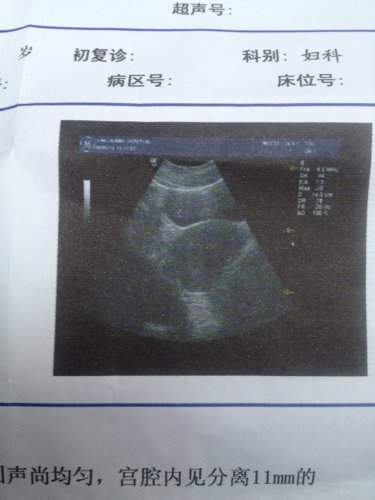

两盒新生化颗粒已经喝完了,药流才六天做了B超复查,阴道现在没流血有褐色液体流出,医生说还有积血,怎么办么????

病情分析: 您好,根据您的描述是有药流后少量宫腔积液的情况 指导意见: 您说的这情况,如果现在已经没有阴道出血的情况,那么可以暂且观察,很多是可以随下次月经来潮自然排出的